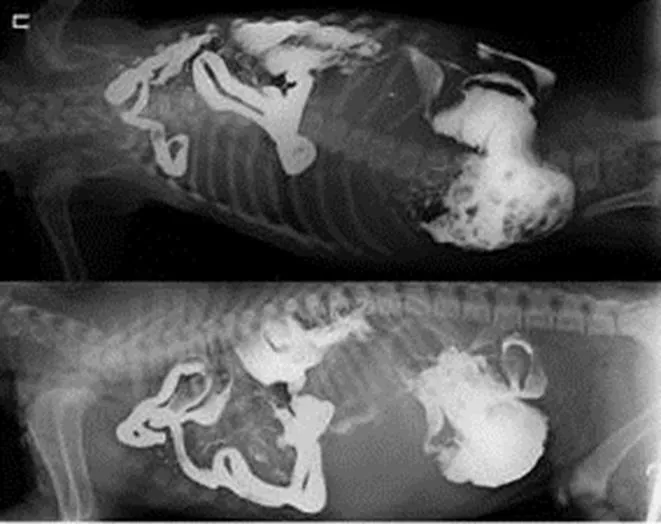

Клинические симптомы травматических диафрагмальных грыж варьируют, снаружи их увидеть не возможно. Около половины диафрагмальных грыж (35-50%) сопутствуют тяжелые респираторные симптомы: учащенное или нарушенное дыхание вплоть до приступов удушья, синюшность слизистых и языка. Характерно для этого состояния также впалая брюшная стенка при вдохе и уменьшение одышки, что ясно проявляется, если животное поднять за переднюю часть тела. Ухудшение состояния наблюдается, когда животное спускается по лестнице. Для подтверждения данного диагноза необходимо сделать рентгенографию грудной и брюшной полостей (рис. 10), в том числе с контрастным веществом (рис. 11), ЭКГ, УЗИ органов брюшной полости.

grizha-10.jpg

Рисунок 10 – рентгеновский снимок кота (в грудной полости просматриваются, наполненные газом петли кишечника).

grizha-11.jpg

Рисунок 11 – Рентгеновские снимки с контрастным веществом (петли кишечника в грудной полости).

Почему необходимо делать рентгеновское исследование при подозрении на диафрагмальную грыжу?

На рентгенограмме можно определить: прерывистость диафрагмального контура, содержимое брюшной полости внутри грудной клетки, смещение грудных структур, смещение органов брюшной полости, расхождение ножек диафрагмы. Трудности при рентгенологическом исследовании заключаются в том, что выпавшие органы могут спонтанно возвращаться в брюшную полость.